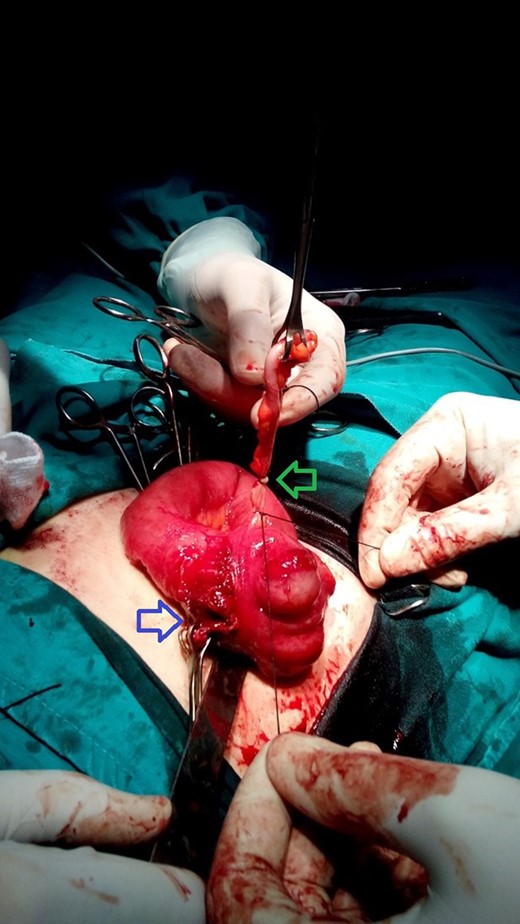

A 30-year-old female presented to the emergency department complaining of abdominal pain. The pain started 48 h ago diffusely in the umbilical region and subsequently migrated to the right iliac fossa. She had associated nausea, vomiting and loss of appetite. There was no alteration in bowel habits. The patient was otherwise healthy and has not undergone any previous abdominal or pelvic surgeries. On physical examination the patient was febrile (39°C) and tachycardic. Examination of the abdomen revealed localized tenderness as well as rebound tenderness at the McBurney point in the right iliac fossa. Laboratory findings showed severe leukocytosis (22 000/ul) with a left shift (neutrophils 88%), and increased C reactive protein (100 mg/dl). Urinalysis did not reveal any specific findings and urine pregnancy test was negative. Abdominal ultrasonography was performed and revealed an appendiceal shield, free fluid, and abscess formation in the right iliac fossa. A definite diagnosis of acute appendicitis was made based on Alvarado score of (10) and a decision was made to perform an open appendectomy via a Rocky Davis incision. Intraoperative findings showed a small quantity of free fluid in the abdomen and two appendices lying on either side of the ileocecal valve, one of them was swollen and erythematous (Fig. 1). The surgeon resected the two appendices. Histopathological examination confirmed the diagnosis of appendiceal duplication. The first specimen showed an inflamed appendix with lymphoid hyperplasia, thickened muscularis and prominent neutrophilic infiltration compatible with acute appendicitis (Fig. 2). The second specimen showed a normal appendix without serosal inflammation, or neutrophilic infiltrate in the muscularis propria (Fig. 3). The tip was present without any lesions. The patient had a full recovery without postoperative complications and was discharged on the third postoperative day.

A photograph taken during surgery. Blue arrow indicates the site of inflamed appendix after resection. Green arrow indicates the second appendix.